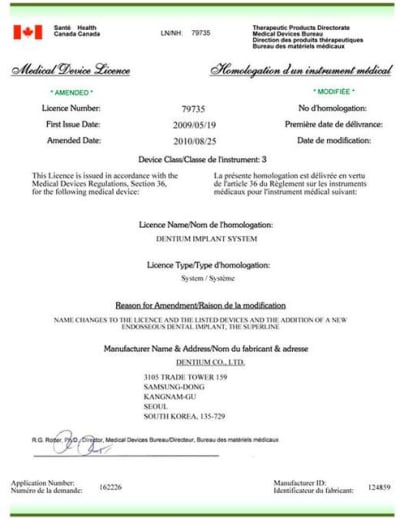

Peut-être que Dentium sera disponible chez moi en 2012.

Apparemment si, même s'il n'y a pas de distributeur local.

s'il aime le "mordant" des biohorizon ou des ID...y a pas photo...même si fondamentalement le superline est un excellent implant...;-)

> fondamentalement le superline est un excellent implant...;-)

Le Superline n'est pas plus mordant que le Astra ?

Pour le Dentium, j'avais envoyé des mails il y a 6-8 mois, jamais de réponse...

le dentium est un implant sympa...mais j'ai du mal avec dès que l'os est dense...sa stab primaire en cas d'os mou est due à sa forme en S, pas au filetage peu agressif et carré et donc peu autotaraudant...ceci explique aussi mes difficultés rencontrées en cas d'os dur car du coup il a du mal, je trouve, à créer son filetage dans l'os...enfin, c'est mon ressenti perso...

sauf qu'il n'y a pas de taraud dans le système dentium... la seule manière de moduler çà c'est de moduler la profondeur d'enfoncement du countersink...pas des plus (pour moi) simple à gérer lors de la chir...quand faut dévisser l'implant pour repasser le countersink pour ensuite remettre l'implant...çà me "gonfle"...enfin bon, moi, j'aime quand c'est simple...